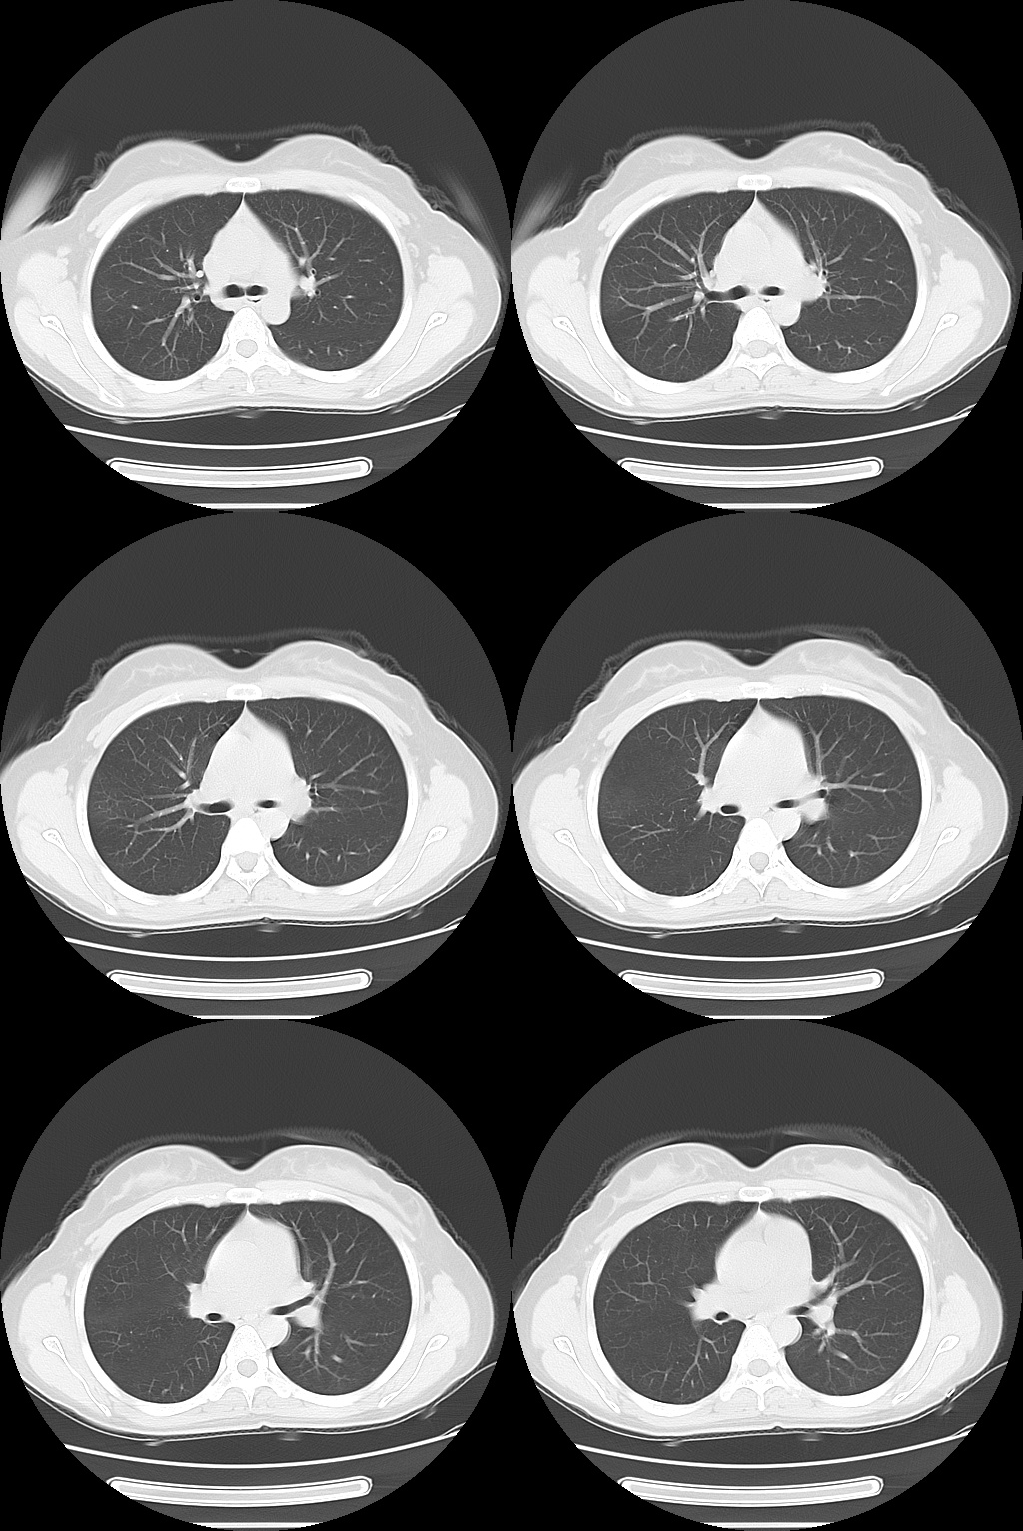

X 线、CT 平扫表现为类似肺炎的渗出性病变或轮廓清楚的肺内结节、胸腔积液、薄壁囊肿 (腔) 或肺大疱及气胸等征象,有的出现支气管阻塞和周围肺不张。如相同肺段在两次经期出现类似肺内改变,而月经期后肺内无异常发现或咯血停止,在排除其他肺部疾病后,可确诊。

患者月经期结束后一周复查 CT